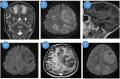

Cerebral aspergillosis is a fungal infection with a bad prognosis. It usually occurs in immunocompromised patients and manifests itself .Cross-sectional imaging reveals suggestive lesions.

Keywords: brain MRI; cerebral aspergillosis –; immunosupression –.